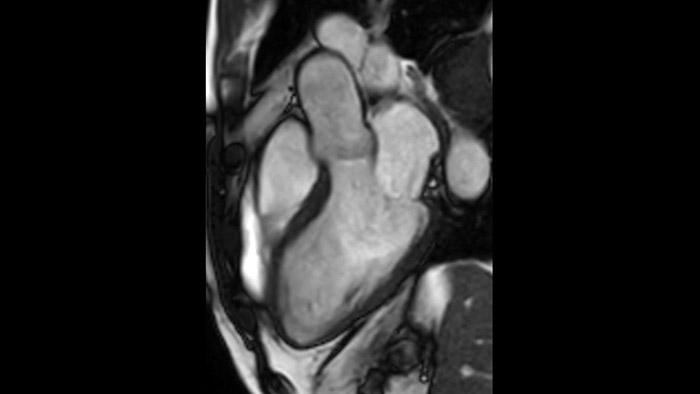

Combinando la smart-sync2 sviluppata dalla NORTHH MEDICAL (un sistema di Doppler a ultrasuoni compatibile con la MRI) con un sistema di RM Philips, abbiamo reso possibile la RM fetale cardiaca per fornire informazioni diagnostiche aggiuntive che possono aiutare nella diagnosi delle patologie cardiache congenite fetali, nel caso in cui l’ecocardiografia non sia sufficiente. Per saperne di più sullo smart-sync e scoprire cosa ne pensano i nostri clienti, clicca qui.

L'utilità diagnostica e prognostica della RM cardiaca è in continua crescita. È possibile valutare l'anatomia e la funzionalità cardiache utilizzando acquisizioni cine, ottenere informazioni sulla perfusione e vitalità del tessuto cardiaco, visualizzare potenziali edema con la sequenza Black Blood, accedere e persino quantificare la caratterizzazione dei tessuti con CardiacQuant.